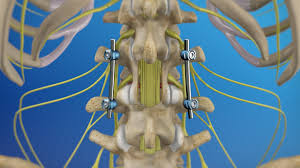

— Our Services

— Our Product

Take a Look at Our Awesome Gallery